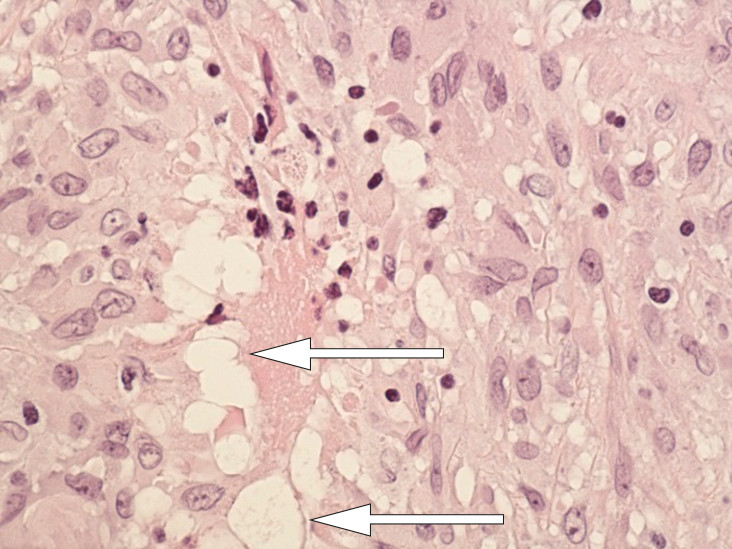

Cytologisk prøve av væsken fra høyre mamma viste uspesifikk kronisk inflammasjon. Det var ingen holdepunkter for malignitet. Undersøkelse av operasjonspreparatet viste fortykket kapsel på høyre side og noe tynnere på venstre. Det var ingen tegn til proteseruptur. Histologisk prøve fra kapselen viste granulomatøs betennelse uten nekrose og utvaskede hulrom i makrofager, forenlig med forekomst av silikon (fig 4, fig 5).

Biopsier fra lymfeknute i mediastinum var tettpakket med ikke-nekrotiserende granulomer, forenlig med sarkoidose. Det var ikke tegn til lymfom eller silikon (fig 6).